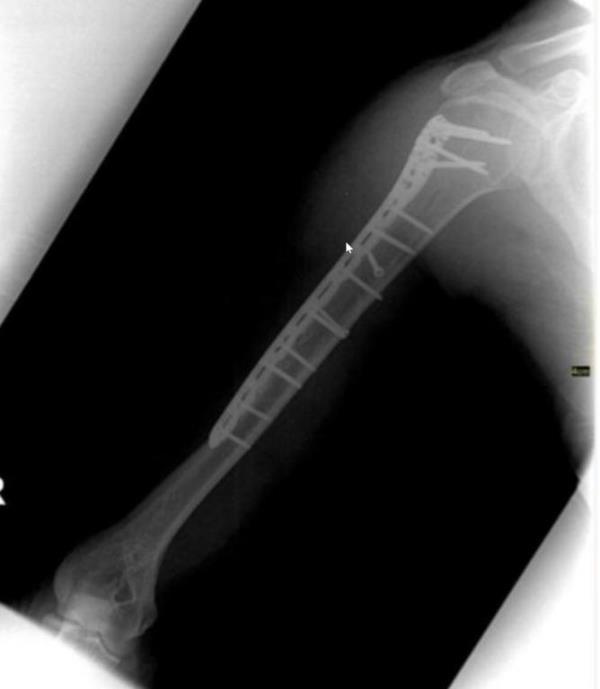

柯蒂斯·布兰斯比当时正在云加山五星级的卡玛·坎达拉酒店度假,他被从车上扔到一堵砖墙上,手臂骨折,从此无法工作。

布兰斯比先生告诉7NEWS,撞击使他飞到一堵砖墙上,导致他手臂上的骨头“粉碎”。坐在他腿上的三岁孩子也被甩出了车外,额头受伤。

这位47岁的父亲说,事故“把我的手臂炸成了碎片”,让它“像一根绳子一样挂在我身后”。

修复骨折所需的手术费用由旅行保险支付,但布兰斯比表示,他仍在努力从9月20日的坠机中恢复过来,现在被诊断出患有复杂的局部疼痛综合征。

Mr Bransby had to undergo immediate surgery to repair the broken arm.